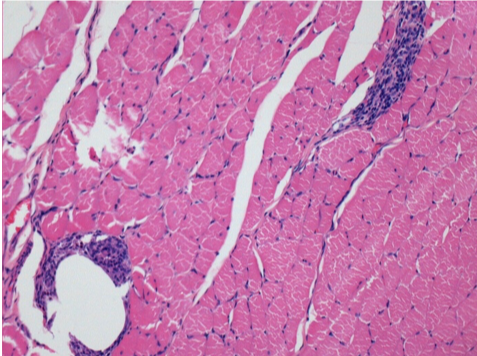

3 months (D90)after Endopeel Injection 0.1ml in the right pretibial muscle.

7 months (D210)after Endopeel IM Injection 0.1ml in the right pretibial muscle.

Complete Restitutio ad integrum after 7 months